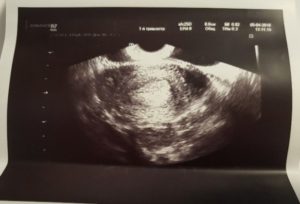

Уже к 6-8 неделе оплодотворенное яйцо становится внедренным в стенку матки. Длинна образованного эмбриона очень незначительна – может составлять около 2-4 мм. Величина плодной яйцеклетки подобна слегка согнутому рисовому зернышку. Появляются задатки рук, ног, они подобны крошечным отросткам, отделяющимся от тельца.

Определить беременность можно посредством УЗИ к 2-3 неделе акушерского срока. Уже с этого периода врач благодаря диагностированию может:

- Определить наличие зародыша;

- Установить количество плодов;

- Заметить внематочную беременность.

Сердцебиение врач способен определить только после 4 недели. На таком раннем этапе обследование назначают беременным только в исключительных случаях: